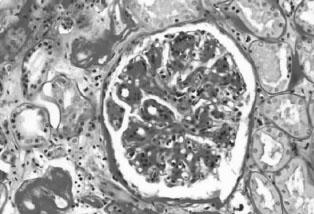

IgA肾病的典型病理表现为:在光镜下常见系膜细胞增生、基质增多(图2—10),常呈局灶节段性分布。IgA肾病轻微者则只有轻微系膜增生,亦可呈弥漫增生(常有局灶节段性加重)。约20%病例可出现新月体,通常不超过肾小球的30%。IgA肾病进行性病例可见球囊基底膜变形、裂解;肾小球基底膜“溶解”。免疫荧光镜下,可看见在肾小球系膜中呈弥漫分布的颗粒或团块状IgA沉积物(主要是IgA1(图2—11)。60%~90%的IgA肾病病例伴C3和IgG沉积,但强度较弱。IgA轻链以λ为主,有J链,无分泌块,通常无C1q和C3沉积。电镜下几乎都可见到细小均一的颗粒状电子致密物,分布于系膜区;若在上皮下或内皮下出现,则可判断为IgA肾病病情严重。上皮细胞足突则常常是正常的。

图2—10 系膜增生性IgA肾病,肾小球系膜细胞和基质增生(PAS x200)